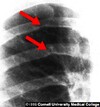

coarctation of aorta dx

-post ductal MC -initial test- BP -doppler echo- confirmatory -imaging: -scalloping of inferior border of ribs due to enlargement of intercostal arteries for collateral supply -"3" sign -red arrows point to rib notching caused by the dilated intercostal arteries -yellow arrow points to the aortic knob -blue arrow to the actual coarctation -green arrow to the post-stenotic dilation of the descending aorta